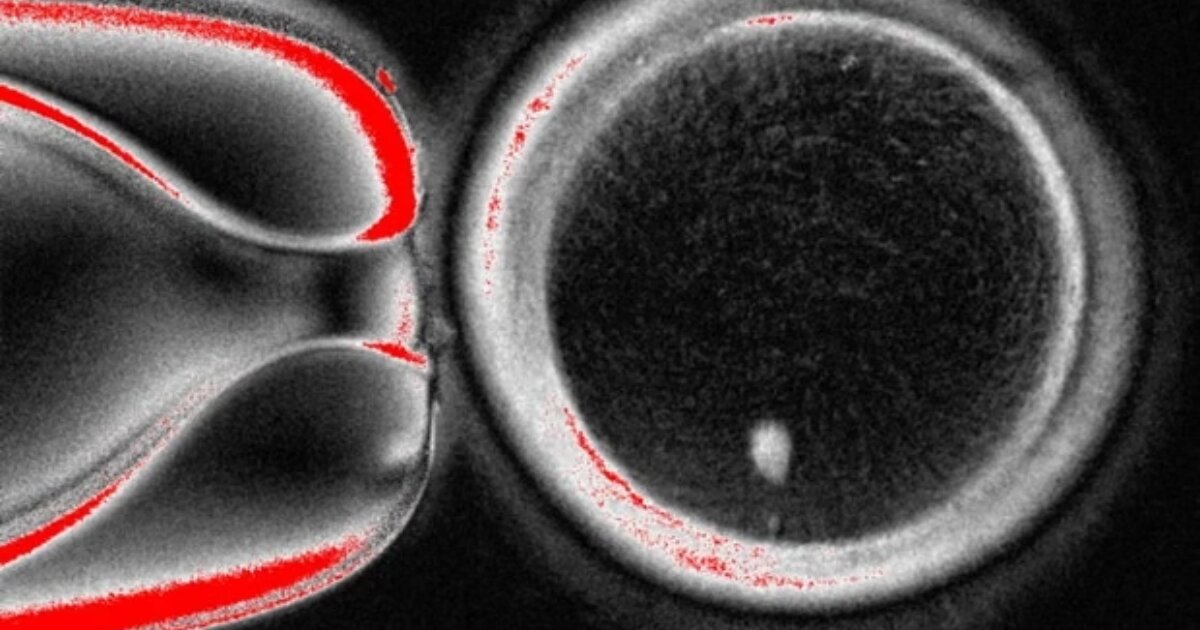

Στην κεντρική φωτο:

Ανθρώπινο ωάριο που δημιουργήθηκε μέσω μεταφοράς πυρήνα σωματικού κυττάρου

Η ομάδα του Όρεγκον ακολούθησε παρόμοια προσέγγιση, συλλέγοντας δερματικά κύτταρα από γυναίκες και αφαιρώντας τον πυρήνα από κάθε κύτταρο. Ο πυρήνας περιέχει τα 46 χρωμοσώματα που φέρουν περίπου 20.000 γονίδια που αποτελούν τον ανθρώπινο γενετικό κώδικα. Κάθε πυρήνας δερματικού κυττάρου τοποθετήθηκε σε ένα υγιές ωάριο δότη, του οποίου ο δικός του πυρήνας είχε αφαιρεθεί.

Σε άρθρο της που δημοσιεύθηκε στο επιστημονικό περιοδικό Nature Communications, η ερευνητική ομάδα περιγράφει πώς ξεπέρασε το πρόβλημα των χρωμοσωμάτων. Μετά τη γονιμοποίηση των ωαρίων με σπέρμα, τα ενεργοποίησαν χρησιμοποιώντας μια ένωση που ονομάζεται ροσκοβιτίνη. Αυτό είχε ως αποτέλεσμα τα ωάρια να μεταφέρουν περίπου τα μισά από τα χρωμοσώματά τους σε μια δομή που ονομάζεται πολικό σωμάτιο, αφήνοντας τα υπόλοιπα χρωμοσώματα να ζευγαρώσουν με αυτά του σπέρματος.